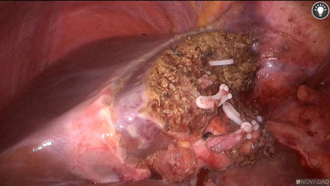

吴全医生此前有实施荧光腹腔镜半肝切除的技术经验,经过精心准备,谨慎操作,最终将6cm的肝脏肿瘤顺利完整切除,同时最大限度的保留了正常肝组织,腹部仅需开4个1cm的小孔,1个3cm左右的切口取出标本,手术核心时间约3小时,出血不多,一周后患者顺利康复出院。

目前腹腔镜下肝脏切除手术是治疗肝脏肿瘤的标配方式,以往在腔镜手术中循肝静脉走行保证劈肝平面不跑偏很考验肝外科医师的功力。新近开展应用的 Pinpoint荧光显像导航技术是利用吲哚青绿(Indocyanine Green, ICG)荧光染料做为标记物,这种染料由肝细胞吸收从胆道排泄,由于肿瘤细胞摄取ICG后比健康肝细胞排泄得慢,易发生滞留,故利用这一特性将肿瘤或要切除的肝段用ICG进行标记,再用700-800nm波长的光波照射,被染料标记部分可发射λ840nm的光波,最后经特制装置接收并转换为荧光或彩色荧光呈现至显示器。借助这漂亮的荧光,肝脏外科医师就能够在断肝的过程中直观地看到需要切除的肝脏与需要保留的肝脏之间的分界线,有了清晰的路标指引,手术刀即能始终保持在正确的离断平面上,不会因为走歪而导致病肝切除不够或健侧肝组织损失过多,可以说荧光腹腔镜是开展微创、精准肝切除的一大利器。